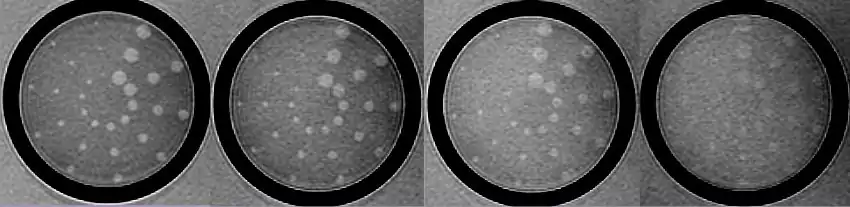

Contrast resolution is usually measured by generating a pattern from a test object that depicts how image contrast changes as the structures being imaged get smaller and closer together. The picture below shows one such set of images produced using the low contrast detectability inserts of the phantom employed in the MRI accreditation program of the American College of Radiology.